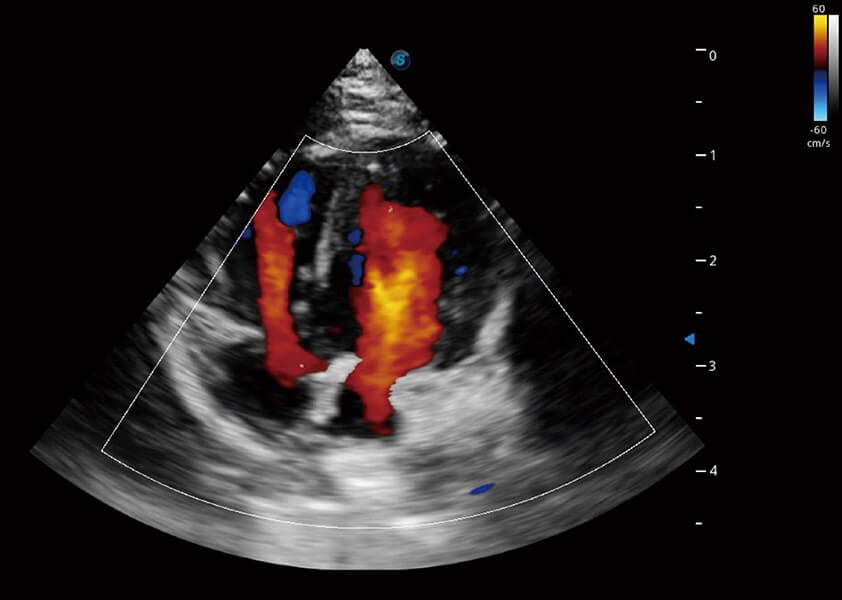

ProPet 60 作為一款高端臺式動物超聲設(shè)備,為動物醫(yī)生的日常診斷提供了一系列貼合動物臨床需求、解決臨床實際問題的高級成像功能。憑借全系列高清探頭,滿足醫(yī)生對腹部、心臟、生殖、淺表、肌骨等成像的所有需求,切實幫助您提升檢查效率,提高診斷信心。